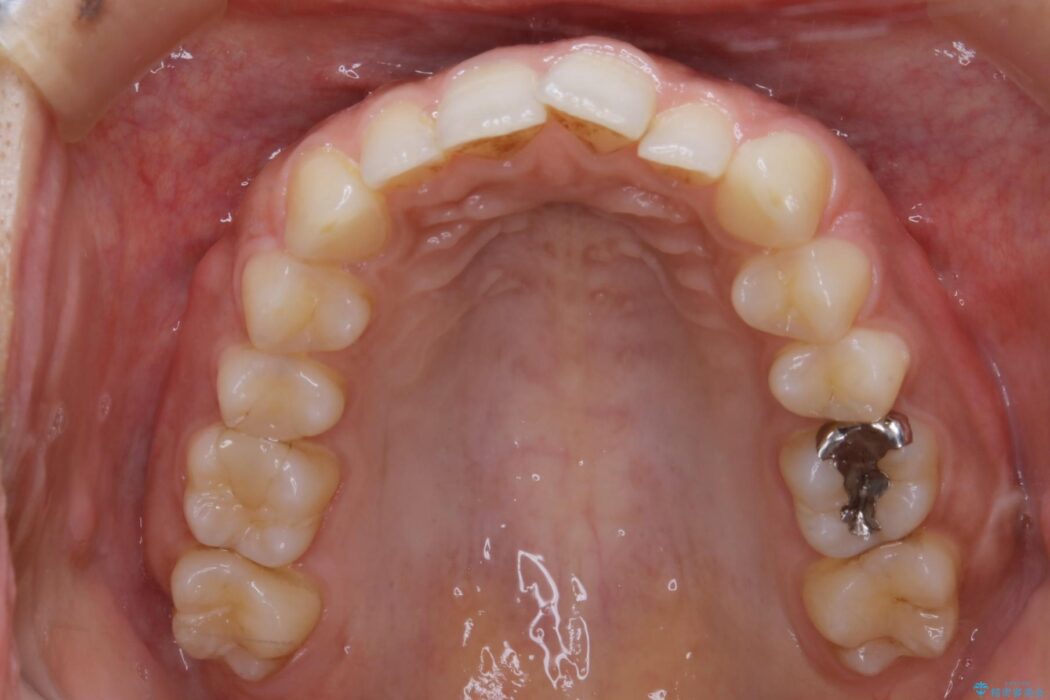

気になるガタツキと噛み合わせを改善したいとご来院されました。

下の歯列よりも上の歯列が前に出ている状態を治すため、マウスピース矯正に加え、患者様にゴムかけのご協力をいただきました。その結果、ガタつきが改善し、上下の噛み合わせが適切な位置で合うようになりました。

歯列弓の拡大

歯並びが悪くなる原因の一つに「歯列弓の狭窄」というものがあります。

奥歯や前歯が内側(舌側)に倒れ込んでしまったり、歯が生えてくる位置が内側になってしまうことにより歯並びのアーチが狭くなってしまうことを言います。

このような場合、歯並びのアーチを拡大してあげるだけでもガタつきを無くすためのスペースがかなり作れることがあります。